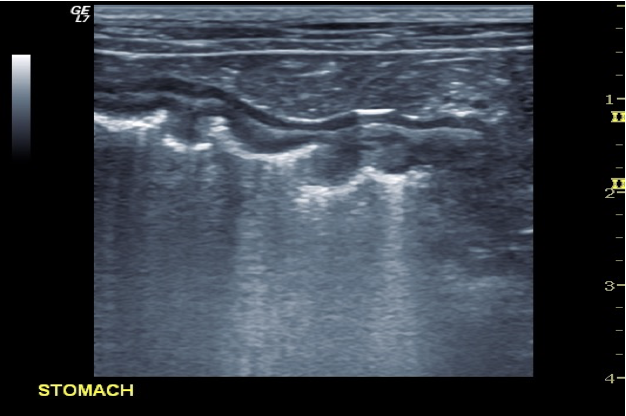

Normal rugal folds and gastric wall layer. Characteristic sub-mucosal, luminal comet-tail artefacts confirm presence of gas within stomach – unable to visualise any gastric detail or content distal to the gas